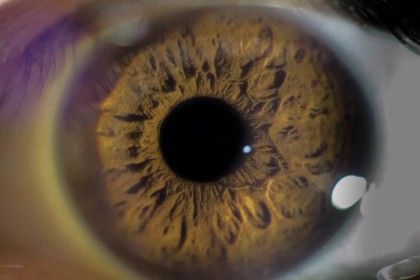

Degenerescența maculară senilă este o afecțiune progresivă care afectează aria centrală a câmpului vizual, prezentă în stadii incipiente la cel puțin o treime dintre vârstnicii de 80 de ani sau mai mult.